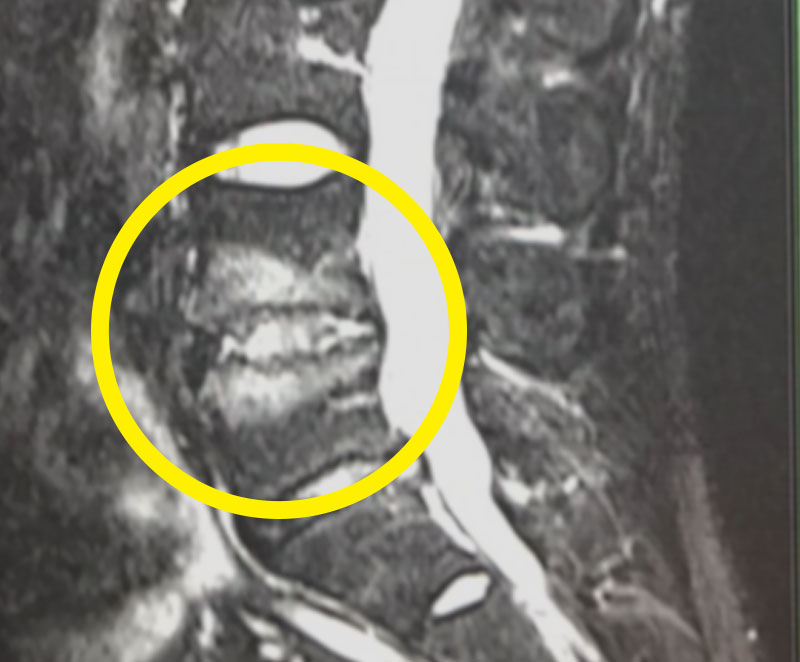

これまで診断や治療が難しかった慢性腰痛の患者さんに対しても、2つの病態に対して全内視鏡下手術で治すことができるようになりました。1つは High signal intensity zoneで、これは、椎間板にできた裂け目です。この部分に内視鏡を入れて、ラジオ波バイポーラで焼灼することで、痛みをぐっと抑え込むことができます。

High signal intensity zone(椎間板の裂け目)